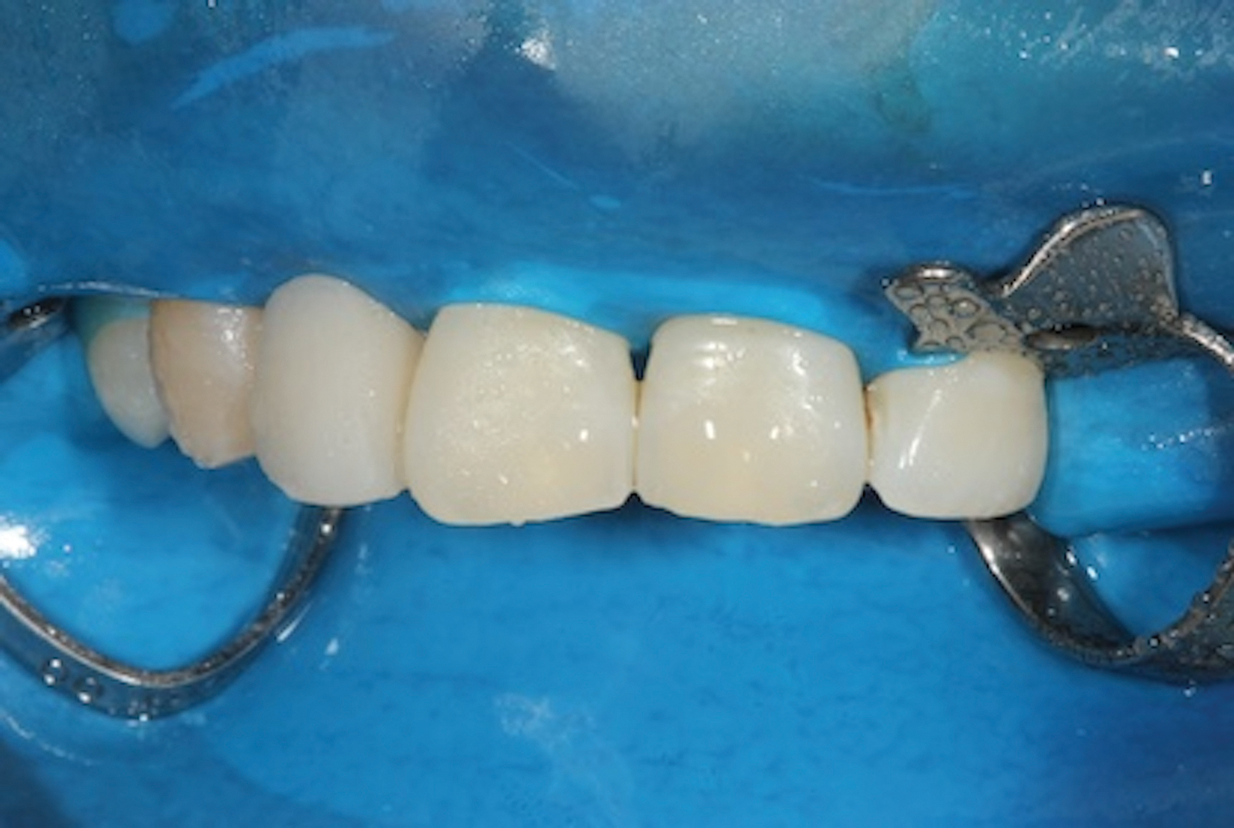

(12.) Final finishing and shaping of the bridge should be performed before removal of the rubber dam, but any final occlusal adjustments should be performed after.

Figure 12

(13.) Immediate posttreatment view of the final fiber-reinforced composite bridge.

Figure 13